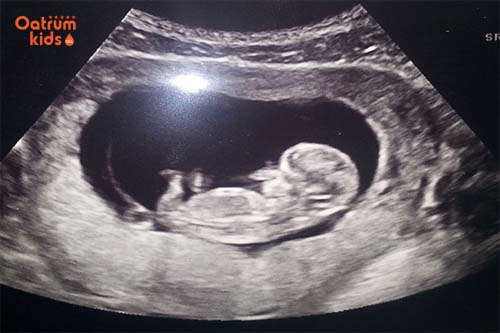

Siêu âm và làm xét nghiệm quan trọng khi thai được 11 tuần.

- Đo độ mờ da gáy: hay còn gọi là đo khoảng sáng sau gáy, giúp cho việc chẩn đoán hội chứng Down sớm hoặc các dị tật bẩm sinh khác nếu có.

- Siêu âm đầu dò: nhằm mục đích kiểm tra tim thai, quan sát hình ảnh thai nhi lẫn tình trạng tử cung của mẹ rõ ràng, đặc biệt là khi mang thai ngoài tử cung.